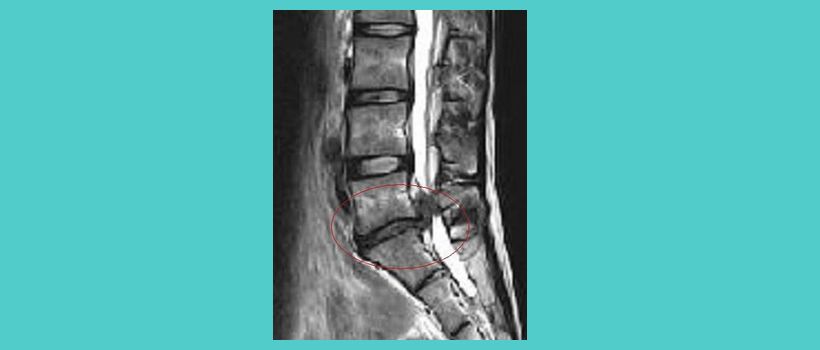

西洋学において腰椎すべり状態は、仕事などで前こごみになりがちの方、腰の曲りがひどいと腰椎が体重の重さに耐えきれず腰椎の一部が前方へズレると言いますが、容態はすべて筋肉が起因して起こります。

この腰椎がズレて前に滑り込むと言われますが、

これらは筋肉が起因して神経根や椎間板或いは、

椎間関節を圧迫して大きな負担を掛ける為に

急性慢性の腰痛を引き起こします。

又、腰椎の滑り込みは背骨の棘突起によって

止まるのですが慢性的に強い圧力が繰り返し掛かると

背骨の棘突起が剥離骨折を引き起す

これを、脊椎分離症と言います。

腰椎は5つの椎骨で成り立っております。

上半身を支える脊柱の中で大変重要な役割を果たしており、上下左右の動きも大きく、大変負担のかかる場所でもある事で椎間板の障害を起こしやすい場所でもあります。

椎間板ヘルニアとは、椎間板の繊維輪に亀裂が入り、内部の髄核が飛び出して神経組織を圧迫する状態です。